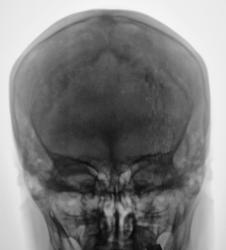

Какие мнения будут, уважаемые коллеги, по поводу выставленных снимков черепа.

Сделали "мягкий" снимок.

Травмы не было. Пациент почувствовал, что "шишка" прогрессивно увеличивает уже в течение 4-5 лет.

Усли не праздничная гематома, то гемангиома.

На мой взгляд, наружная пластинка (в том месте) уже частично "поедена"